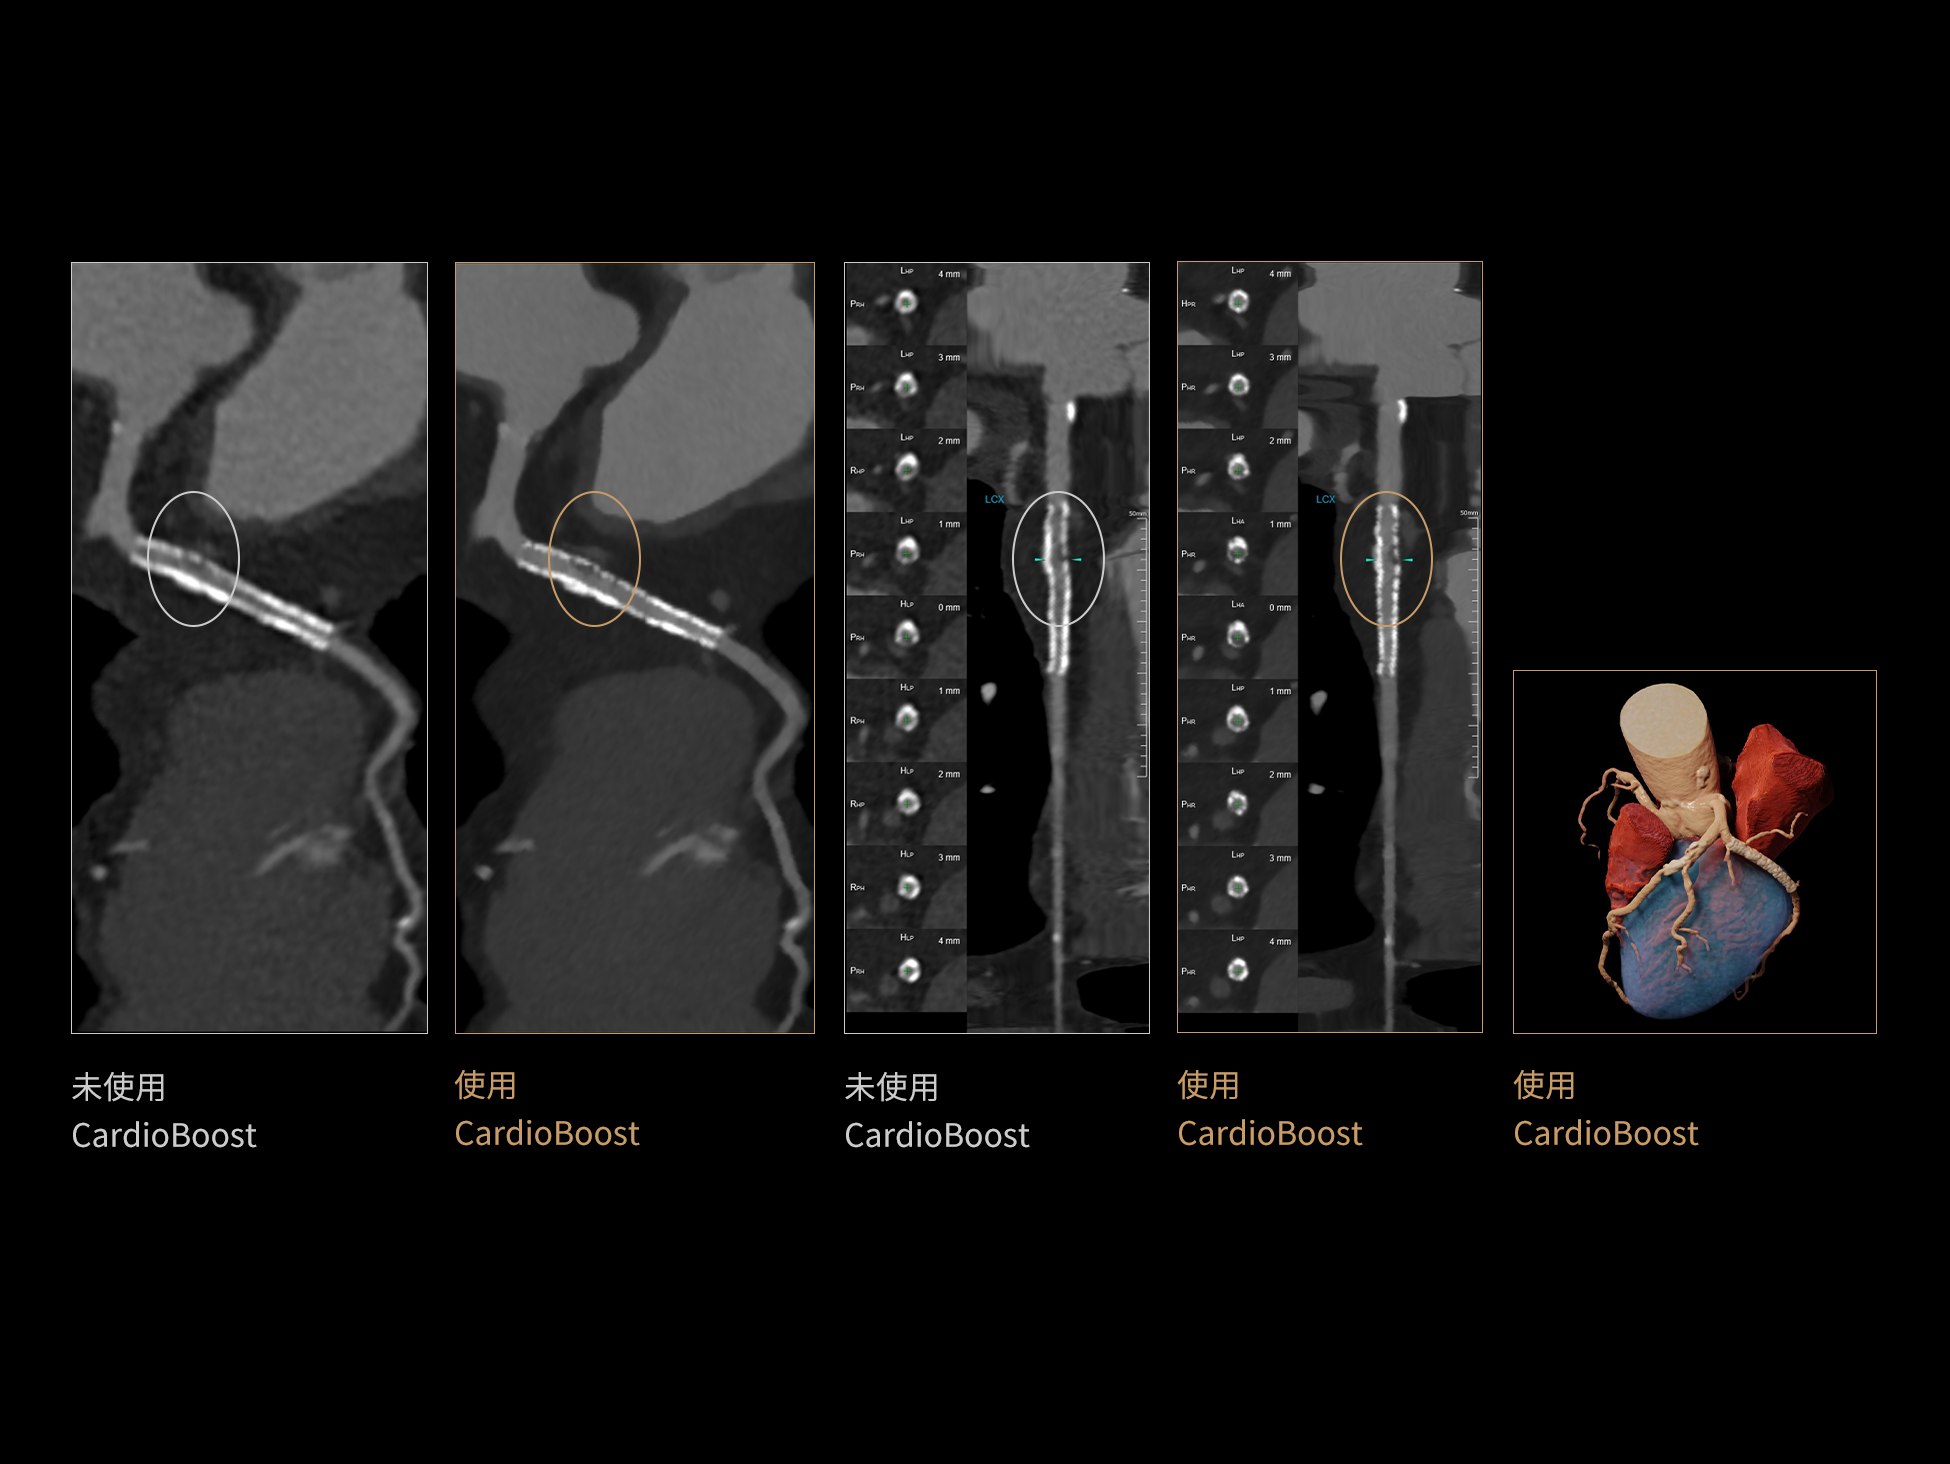

CardioBoost:专属网络设计,重塑心脏影像表现

uCT 868 搭载联影最新一代 uSense 人工智能平台,将智能化深度融入 CT 扫描全流程,从感知细微生理运动到精细结构探测,再到多场景诊疗优化。以 AI 为核心驱动力,uSense 重塑成像各环节,打造高效、高清的智慧扫查体验。在心脏成像领域,uSense 结合宽体探测器、心脏专研AI重建算法与AI冠脉运动追焦技术,在保持低剂量的同时,有效抑制运动伪影,精准呈现软斑块、混合型斑块及支架细节,助力冠脉成像惠及更多患者。针对多科室疾病临床应用场景,uSense 平台提供全方位的智能解决方案:包括头部运动伪影智能校正、金属植入物伪影抑制、扫描视野扩展等先进算法。这些创新技术使 uCT 868 能够构建覆盖全场景的智能诊疗体系,持续拓展 AI 赋能医学影像的边界。